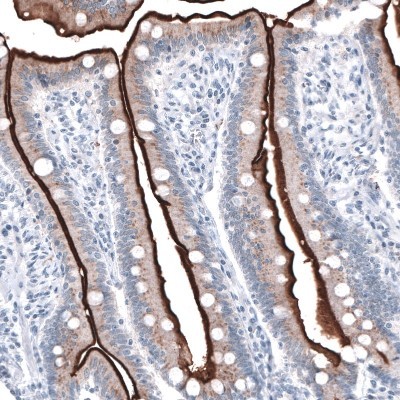

- Immunohistochemistry-Paraffin: ACE-2 Antibody (CL4035) [NBP2-59037] - Staining of human small intestine shows strong positivity in apical membranes of glandular cells.

- Immunohistochemistry-Paraffin: ACE-2 Antibody (CL4035) [NBP2-59037] - Staining of human duodenum shows strong positivity in apical membrane of glandular cells.